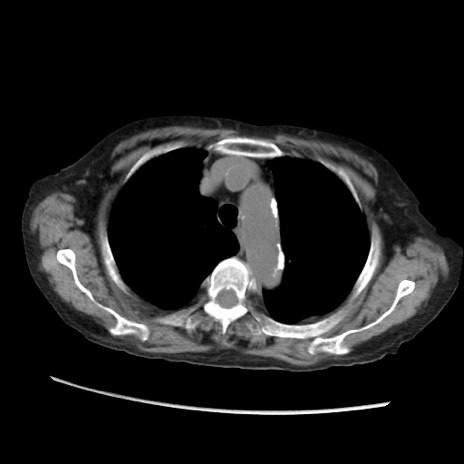

冠状断像

【症例】80歳代 女性

【主訴】腹部膨満感

【現病歴】他院にて肝硬変にてフォロー中。1週間前から便秘、腹部膨満感、臍部腫瘤あり受診となる。

【既往歴】肝硬変

【身体所見】腹部膨隆あり、皮膚変化なし、疼痛なし。

【データ】WBC 4600、CRP 0.25